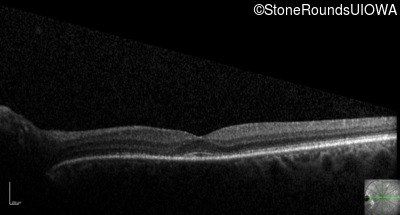

Optical Coherence Tomography - Right - 20/40 -2 sc

Exemplar / OCT Stack